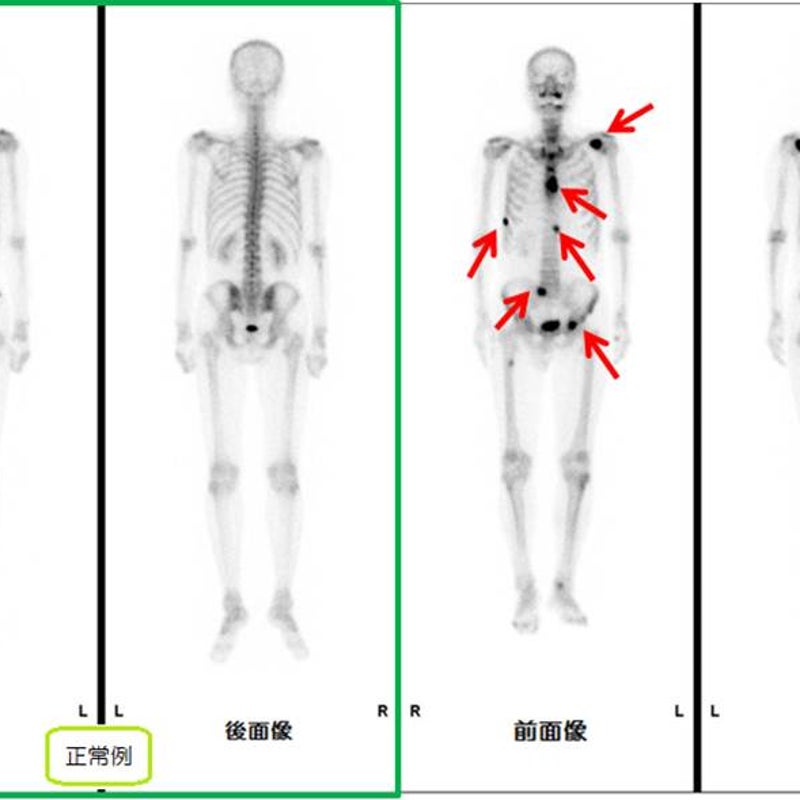

全身骨シンチグラフィ 乳癌 肺癌 前立腺癌等の骨転移病巣の検出

全身骨シンチグラフィ 乳癌 肺癌 前立腺癌等の骨転移病巣の検出

骨シンチグラフィによる骨転移の診断 Bone Scan Ct Mri画像診断